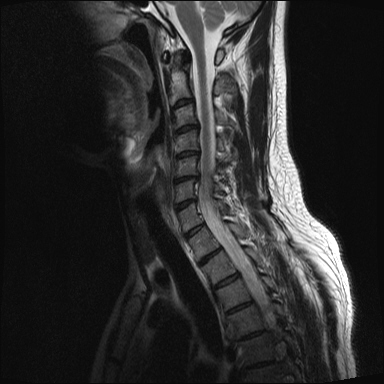

ȸ ϸ鼭 ۼ Դϴ. Ű 172 72 35 ˰Ե ͳ õ ijħ ǥغ ϱ ȣϽ 1C.ڵӸ 1C.ٸǷ 1C.ټ Ǹ 1C.ٱ () 1C.߷ () 1C.Ƿ () 2C.ھȱ, 2C.ڴ 2C.ھ˷⼺(˷) ḷ 2C.ٴ, 2C.ٰḷ 2C., 2C.ٺ, 2C.ٸ 2C.پ˷⼺(˷) 3C.ġ Ű 3C. 4C. 6C.ڸ 6C.ھ Ḳ 6C.ڻ 1T.ȣ 4T. 3T.ȯ, 5T.ȯ ҷ, 6T.ټ 6T.ٽƮ 9T.˷ 10T.ٸǷ 2L. 㰡 2L.ȣ 3L. 3L.ڹ 4L.° 4L.ھƷ 4L.ڿ, 4L.ڵ Ʒ 5L.ڴٸ Ʒκ̳ 5L.ڹ߸̳ õ().¦ٸ ()ũ( ߰Ż) Ը Ͽ ũ(߰Ż), ũ(߰Ż)ġ, , Ḳ , , Ḳ ġ ȱ ǰϰų ڸ, , ڰ , , Ǵ ġ ô ¦ٸ(ٸ̰ ٸ) , 㸮 ̳ ġ Ƹ ġ ħ ߷, , нɷ 帶, ɱٰ, ɺ ڸǥغ ǥغ ϰ ߴ ġ 1. ũ 1) ߺñ: 1 Ӹ ־ ʹ 2)˻ : ** x-ray MRI Ȯ 3,4,5 ũ ̸, Ư 4 ũ ¦ Ƣ . 3)ġ: Ű漺 , ġḦ ʾҰ, Ư ǿ ħ °, Ȱġ(Ȳ,ħ, ȸ ) . 4)ġ : 1.Ͻ ȿ ־, ð 2. 㸮() 1) ߺñ: 3 ϱ ٳѱ⸦ ڱ 㸮 , ģ ƮĪ شٸ 㸮 ȭ ƮĪ Ʋ . 2)˻ : ǿ 㸮 ġ . 3)ġ: ħ ȰġḦ 4)ġ :Ͻ ȿ ־ ɰų 㸮 3. ڰ 1) ߺñ: ڰ̰ ִ Ȯ 5 Ǵܵ 2)˻ : 6~7ð 2~3ð ڸ , ȣ 3)ġ: ġḦ ް , ڰ *** ߿ Ƽ ϰ 4)ġ : ڸ 4. 1) ߺñ: 2~3 ְų Ͻ ־ 2)˻ : ˻縦 ʾ, ʰ ô ó 3)ġ: 4)ġ : 5. ô 1) ߺñ: 3 ڿ ɾƼ ٸ µ ٸ ª 2)˻ : 7 Ȱ X-RAY ణ ô ִٰ Ǹ 3)ġ: ġ 4)ġ : Ͻ 6. (˷ ḷ) ȱ 1) ߺ: 5 2)˻ : Ű 3)ġ:1~2 ѹ ް Ⱦ ֱ ְ 4)ġ : , ħħϰų 7. , Ѽ ȣ ߺñ: ɸ Բ ڰⰡ , ڸ, ä, 2)˻ : Ḧ ʾ, ڰ Ⱑ ư, Ѽ Ҵ Ȳ µ ϰ ȸ ȭ ˷ֽ ǥغ ϴ ڸ ϴ. 㿡 ħ ȸԲ ˷ֽ Ư ġü ġὺƮĪ Բ ġ ȭ ʰ ȸǴ ڼ ϴ ϴ. ˷ֽ ͵ ̳ ǰ ͳݿ ִ ٸ Դϴ. ϴ ȭ Ÿϴ. ϴ. پٰ ϴ. ϴ پų ϴ. 30и 30 ̻ ϶ ϼ̽ϴ. 30иٴ ϰ ҷ ߽ϴ. Ȳ ٷ ϴٰ ٽ ϴ. ķ 鵵 Ÿϴ. γ ȸԲ ڵȽϴ. ٽ ȭּż Ȳ ϰ ʰ ּ̰ ڼ ణ ߸ϰ ־ ֽð ʰ ˷ּ̽ϴ. ȭ Ŀ ߰ ȭ ߾ ߴµ ϴٰ 1 ȭ ѹ ʾҾϴ. ˷ֽ ˷ֽ 뿡 ణ ̴ ε ̼ϰ ٸ ̷ Դϴ. ʰ ϴ ڼ ü ٽ ϰ ˷ּ̰ а ߴص ϰ ˷ֽ θ ϶ ϼ̽ϴ. ˷ֽŵ Ȱ ϰ غ ı øڽϴ. ȸ 㵵 ű Դϴ. ۼ ıԴϴ. http://najari.kr/Board/index.php?Code=free1&No=5141&action=View&st=&sn=&sc=&Keyword=&Page=1 |